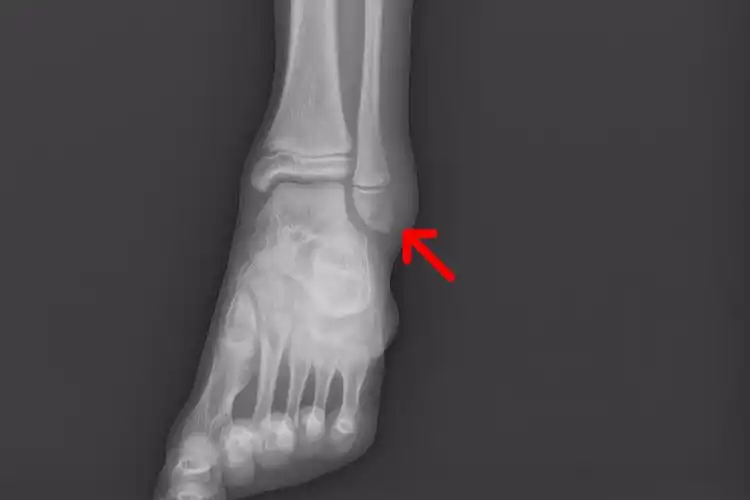

右外踝(腓骨远端)骨折康复记录

外踝为什么受伤的总是我